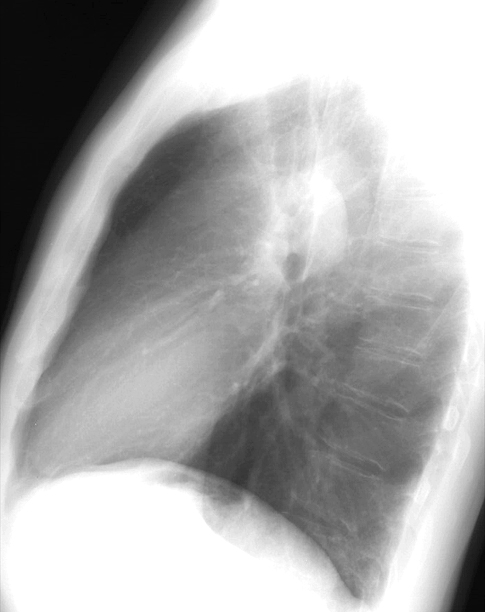

Pulm Stenosis Lat